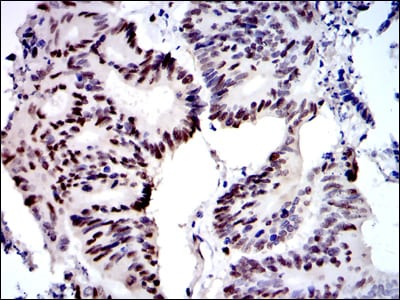

Immunohistochemical analysis of paraffin-embedded human ovarian cancer tissues using MCM2 mouse mAb with DAB staining.

Immunohistochemical analysis of paraffin-embedded human colon cancer tissues using MCM2 mouse mAb with DAB staining.